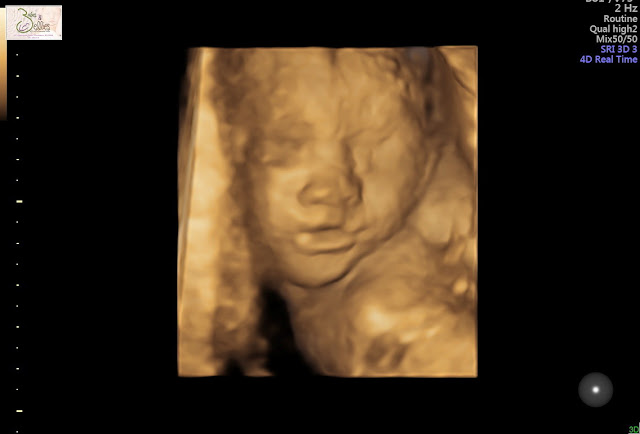

Now, I only paid for 2D...but they showed us 3D!! Look how cute she is! I couldn't see the lower half of Tim's face because of the mask requirement but afterwards he told me he smiled the entire time. I could see the absolute joy in his face though, it was such a special moment.

Of course I had only seen her in 2D up until this point so this gave me a better idea of what she actually looks like. It's still hard for me to get a good idea of what she will look like when she's on the outside. Our ultrasound tech was amazing and really took her time showing us everything. She showed us her foot that has been resting on my bladder (yup! knew that was happening!!) and showed us that she had her other foot pulled up but her face. She was trying to suck on the cord and also had her hand up by her face and was trying to get her thumb in her mouth again.

Her lips looked so full and I do think she has my nose, but it's hard to tell for sure! The ultrasound tech also told us to come back again so we could see her better when she's bigger. I am not sure that we will because it is pricey but it's nice that they offer multiple sessions if you'd like to do that.